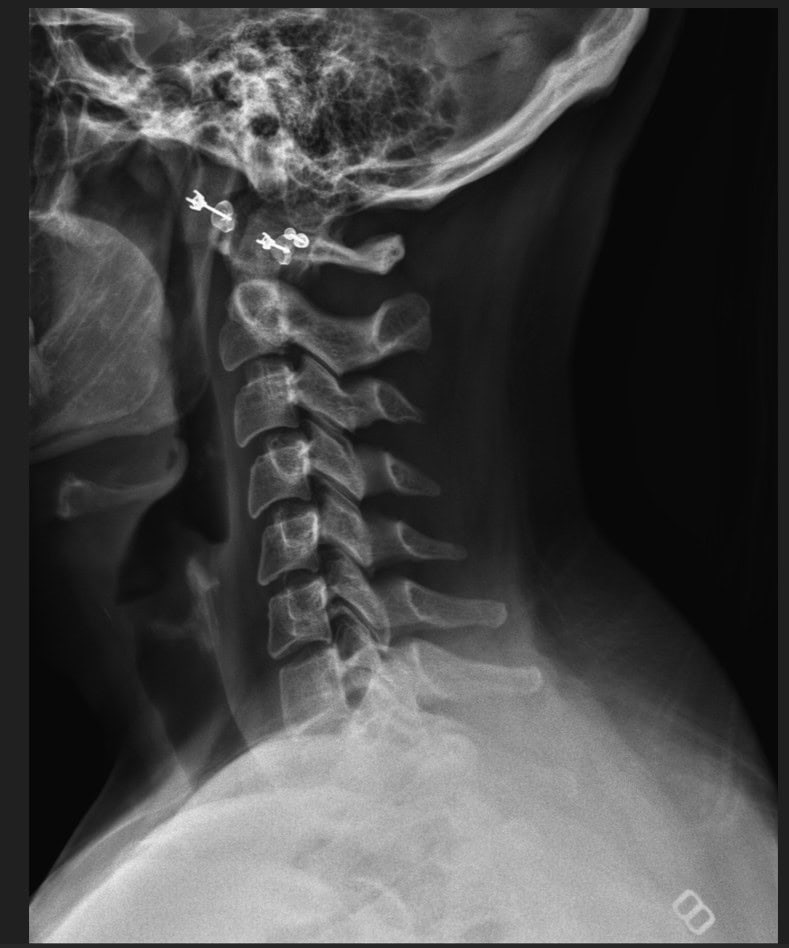

Pre Scan

Post Scan